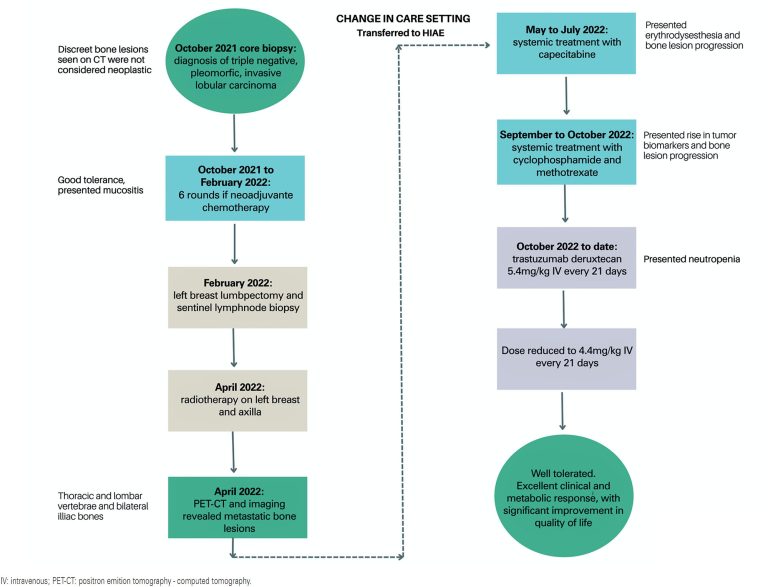

Abstract Breast cancer is one of the most prevalent and heterogeneous cancers worldwide; however, it remains a complex and enigmatic disease. Advances in targeted therapies combined with increasing knowledge about tumor subtypes and molecular profiling have placed precision medicine on the frontier of oncological treatments. The recent classification of certain HER2 tumors as HER2-low, along with emerging evidence from studies using antibody-drug conjugates to target specific tumor profiles, highlights the relevance of this case study. This report describes the treatment […]